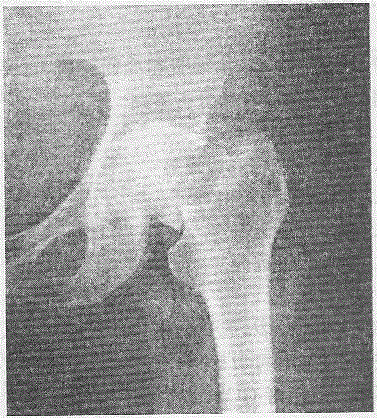

问题 女性,75岁,摔伤致左髋部疼痛、肿胀、活动受限1小时,X线检查如下图所示,断端无明显移位。 首选的治疗方法是

选项 A.人工髋关节置换 B.加压空心钉内固定 C.DHS D.三翼钉内固定术 E.保守治疗

答案 B